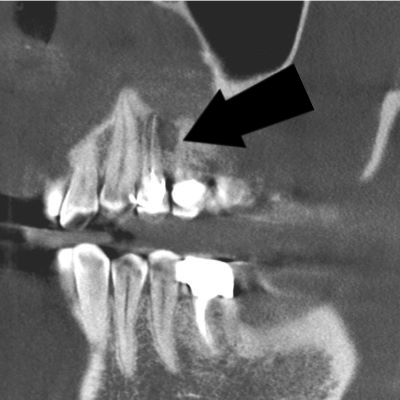

We offer state of the art 3-D x-ray imaging which allows a superior diagnostic level to 2-dimensional imaging. This imaging allows us to find pathology and plan implant cases with a level of precision beyond anything we could imagine 10 years ago.

The patient was having vague pain in the upper left. The 2 dimensional xray appeared to be within normal limits.

3-D x-ray shows an obvious dark shadow indicating an abscess.